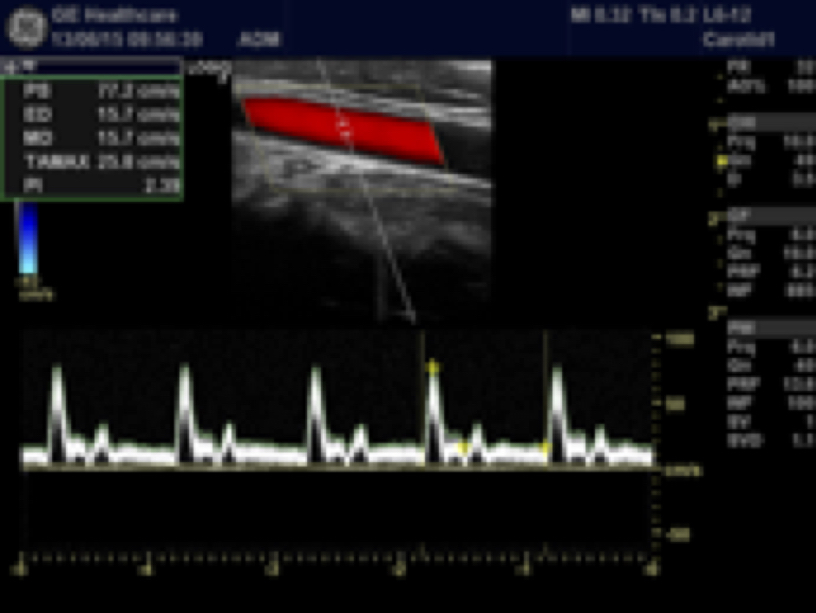

ECÓGRAFO DOPPLER COLOR COMPACTO MARCA GENERAL ELECTRIC HEALTHCARE

MODELO LOGIQ V2

Ecógrafo multidisciplinar compacto digital que puede incorporar transductores convexos, lineales y sectoriales. Tecnología General Electric de alto nivel en un equipo de tan solo 6 Kg. (Incluyendo Bateria). y reducidas dimensiones Flexibilidad, movilidad y altas prestaciones. Con capacidad de trabajar con sondas de hasta 13 MHz de formatos lineal, convex, microconvex y sectorial.

- Doppler Color

- Doppler Pulsado

-SONDA LINEAL 12L-RS